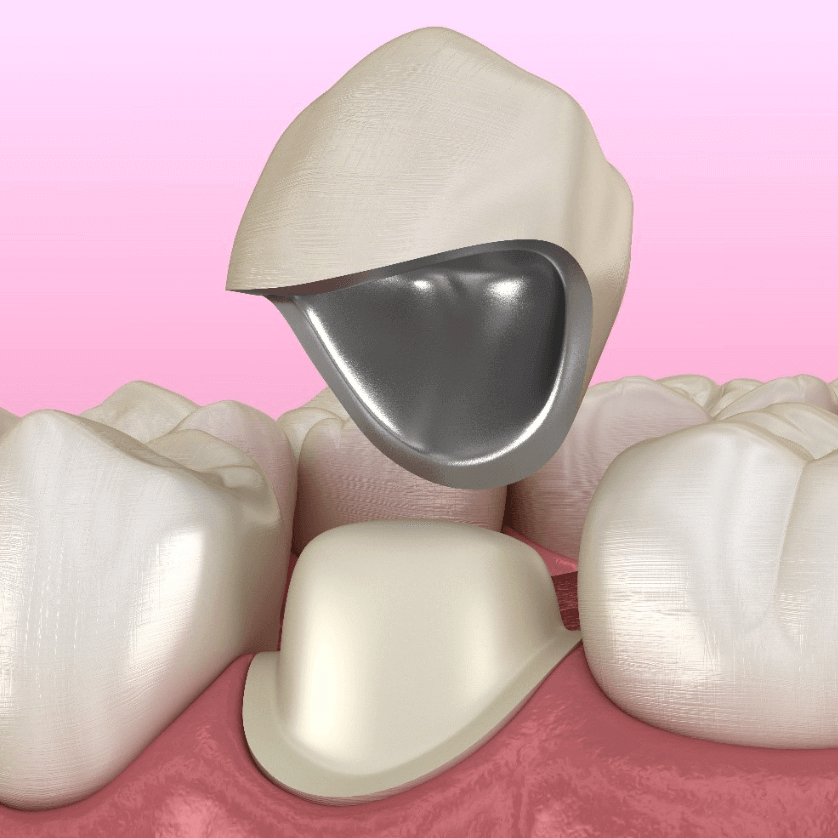

Coronas

Funda que cubre por completo un diente dañado debilitado o tratado endodonticamente para devolverle su forma, tamaño, resistencia y función.